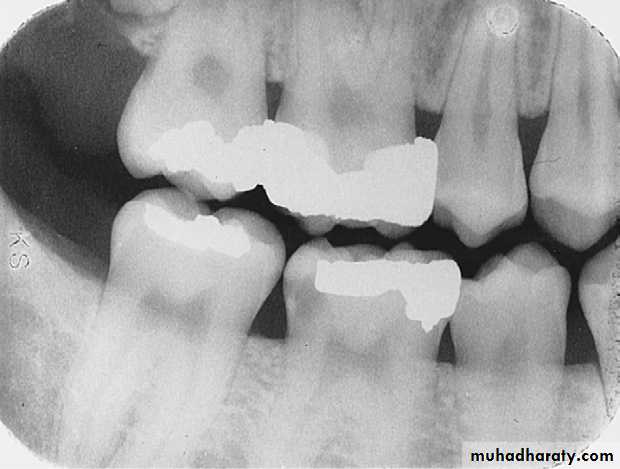

Interproximal Caries (Severe)

extends through enamel, through dentin, and more than half the distance toward the pulpSevere Interproximal Caries

A severe carious lesion on the distal surface of the mandibular first molar.

Severe lesion

Rampant CariesRampant caries is advanced and severe caries that affects numerous teeth

Rampant caries is typically seen in children with poor dietary habits or in adults with decreased salivary flow.